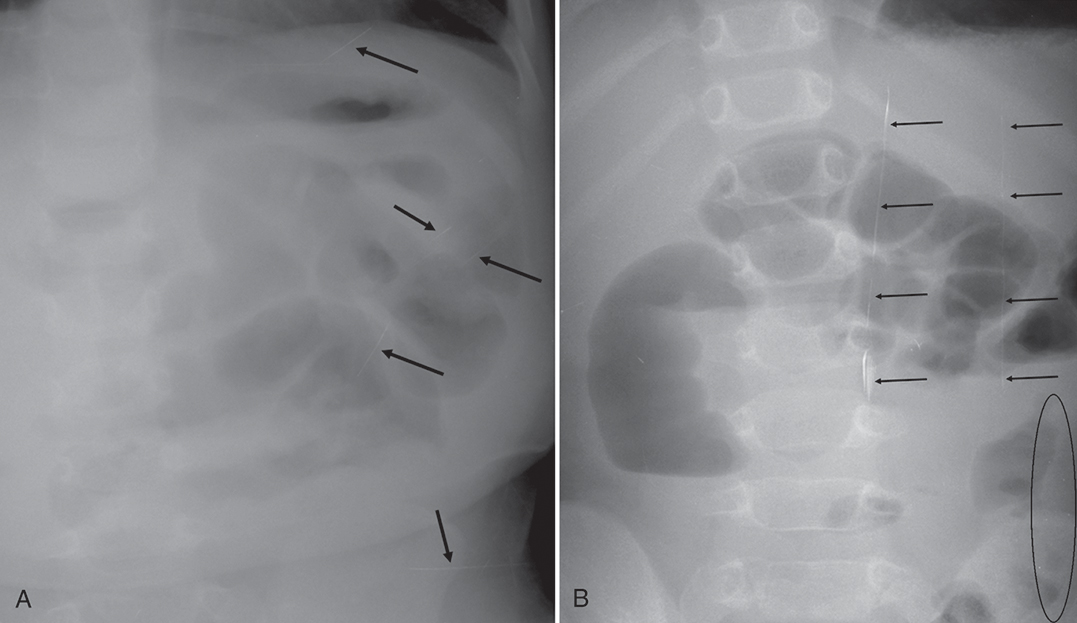

When exposing a patient, the larger the volume of tissue being irradiated, the more scatter will be produced. Although the use of a grid absorbs the scatter that exits the patient and affects latent image formation, properly used collimation reduces the area of irradiation and the volume of tissue in which scatter can be created. Collimation is the reduction of the area of beam that reaches the patient through the use of two pairs of lead shutters encased in a housing attached to the X-ray tube. Collimation results in increased contrast resolution because of the reduction of scatter. Through postexposure image manipulation known as shuttering, a black background can be added around the original collimation edges, virtually eliminating the distracting white or clear areas (Fig. 4.21). However, this technique is not a replacement for proper preexposure collimation. It is an image aesthetic only and does not change the number or angles of scatter. There is no substitute for appropriate collimation because collimation reduces patient dose.

Insufficient collimation can result in an improper calculation of the exposure indicator. This may result in a misrepresentation of the displayed image (Fig. 4.26).